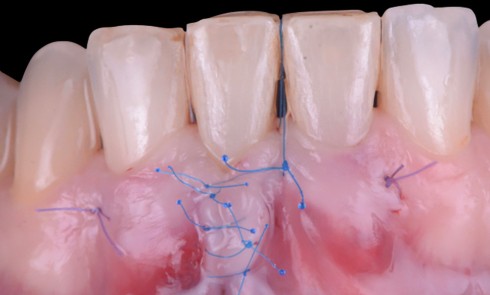

Nous décidons d’entreprendre une thérapeutique initiale parodontale classique dans tous les secteurs, y compris l’extraction de 24, un bridge de 45 à 48 avec 46 en pontique, un bridge complet de contention de 17 à 27 sur 11 piliers dentaires et une greffe épithélio-conjonctive sur 31. Cette dernière ne sera jamais réalisée. Le bridge maxillaire permettra de réduire le surplomb antérieur et d’améliorer le sourire de la patiente, ce qui constitue l’une de ses demandes.